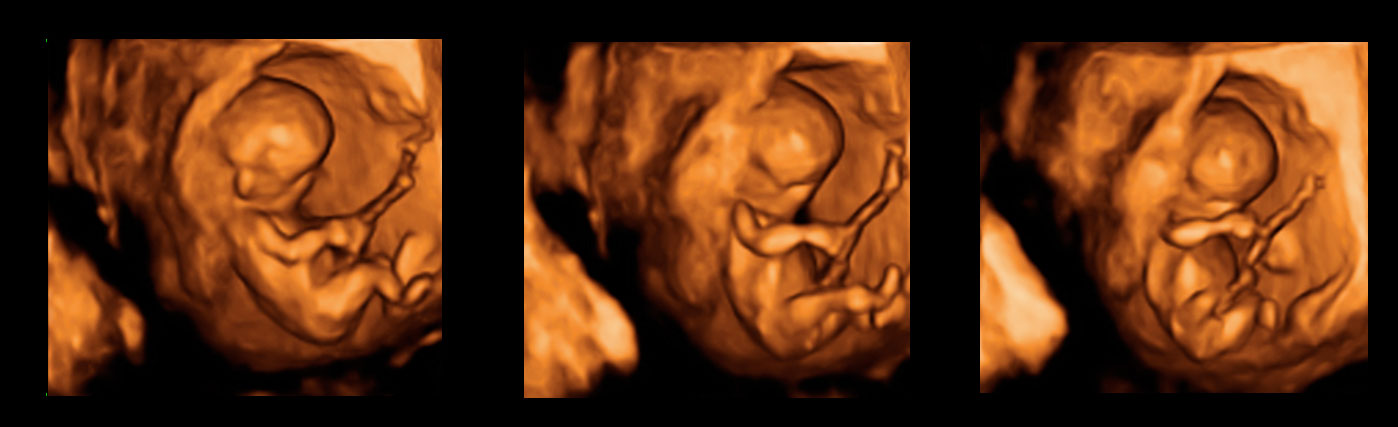

Ecografías de la semana 12: El cribado del primer trimestre

• Medida del pliegue nucal. El aumento de la translucencia nucal es el mejor parámetro que existe en la actualidad para detectar posibles fetos con síndrome de Down u otras alteraciones cromosómicas.